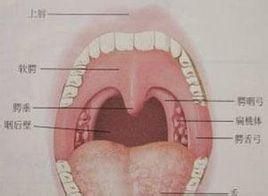

急性咽後壁膿腫多見於1~3歲嬰幼兒,成年人極少見,身體虛弱多病和營養不良的小兒最易患此病。臨床表現為發病急,初有畏寒、發熱、咽痛、不願吸乳、進食,日益加重;咽部因膿腫而共鳴腔縮小,說話含糊不清;咽部腫脹隆起使氣道變窄,故呼吸不暢;頭常偏向一側,頸部僵直,轉頭時肩部、軀幹一同轉向,藉以減輕咽痛和改善呼吸,進食時常嗆入鼻腔或吸入呼吸道引起劇烈咳嗽。